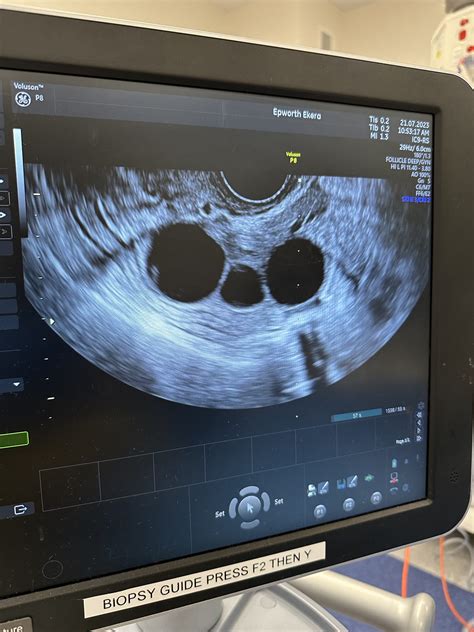

Understanding the internal mechanisms of reproductive health can often feel like deciphering a complex medical puzzle. One of the most common diagnostic tools used by gynecologists and fertility specialists is the pelvic ultrasound, which provides a window into the ovaries. When you undergo this procedure, your physician will carefully evaluate the follicles in ovary ultrasound images to determine your ovarian reserve, check for ovulation, or investigate conditions like Polycystic Ovary Syndrome (PCOS). These small, fluid-filled sacs are the home of your immature eggs, and their size, number, and appearance provide critical data about your reproductive potential.

Ovarian follicles are essentially tiny, functional cysts located within the ovaries. Each follicle contains a single oocyte (immature egg) surrounded by specialized cells. Throughout your menstrual cycle, these follicles grow under the influence of hormones like Follicle-Stimulating Hormone (FSH). During a typical cycle, a “dominant” follicle emerges and eventually ruptures to release the egg during ovulation. When a technician performs a follicles in ovary ultrasound, they are looking at these structures to assess the health and activity of the ovaries.

Most follicles in ovary ultrasound procedures are performed via the transvaginal route. This involves inserting a thin, ultrasound wand into the vagina to get a high-resolution view of the ovaries, which are located deep in the pelvis. By being closer to the ovaries, the sonographer can produce a much clearer image than a standard abdominal ultrasound could provide. The procedure is typically quick, usually taking less than 15 minutes, and is generally not painful, though some mild pressure may be felt.

When reviewing your scan results, your doctor will look at specific characteristics of the follicles. The size of the follicle is a significant indicator of its stage of development. A follicle ready for ovulation usually reaches a diameter of 18 to 24 millimeters. If you are undergoing fertility treatments, your medical team will chart these sizes meticulously.

In cases of PCOS, the follicles in ovary ultrasound will often reveal a high number of small antral follicles. Because the hormonal signaling in PCOS is irregular, these follicles often stop growing at a small size rather than maturing into a dominant, ovulatory follicle. This creates the characteristic appearance of multiple, small fluid-filled circles lining the periphery of the ovary. This visual finding, when combined with blood tests and physical symptoms, helps clinicians confirm a diagnosis.